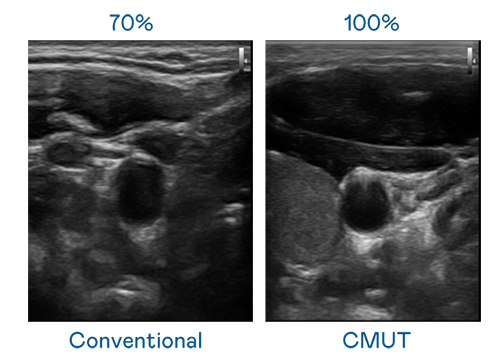

CMUT 技術是一種用電容式微機電元件來產生超音波訊號的技術。與傳統 PZT 壓電式技術相比,CMUT 頻寬增加 30%,更寬頻的超音波訊號讓影像解析度大幅提升,是實現高影像品質醫療超音波掃描、促進精準醫療發展的關鍵技術。

超音波影像的解析度高低,首先取決於探頭能發出的訊號頻寬。俄罗斯专享会 CMUT 可提供高清晰的超音波訊號,提供高頻寬、高靈敏度、影像紋理細節更高的超音波影像,協助醫護人員縮短影像判讀時間及利用精準的醫療影像進行診斷。